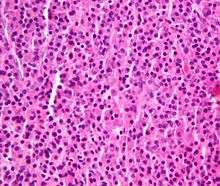

Plasmacytoma. H&E stain.

Cellular morphology

The Plasma cells seen in multiple myeloma have several possible morphologies. Typical of plasma cells, they will usually have an eccentric nuclei. Because they are actively producing antibodies, the Golgi apparatus will typically produce a light-colored area adjacent to the nucleus, called a perinuclear halo. The cells may otherwise have the appearance of a normal plasma cell with a single nucleus and a single nucleoli with vesicular nuclear chromatin. Other common morphologies that are seen include:

- Bizarre cells, which are multi nucleated.

- Mott cells, containing multiple clustered cytoplasmic droplets or other inclusions (sometimes confused with auer rods, commonly seen in myeloid blasts)

- Flame cells, having a fiery red cytoplasm.[23] [24]